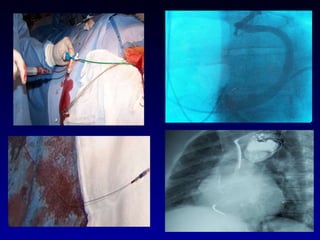

Efectos De La Terapia De Resincronización Cardíaca a Largo Plazo.   Castro Villacorta H, Ortiz Avalos M, Rodriguez Diez G, Ramírez Machuca J, De Haro Lafarga S, Robledo Nolasco R.  Estudio Longitudinal Observacional durante el periodo del 12/04/99 al 14/03/08. Se incluyeron 85 pacientes. Clase funcional II,III ó IV de la NYHA Diámetro diastólico del VI ≥ 55 mm FEVI ≤ 35% QRS angosto o ancho Parametro ecocardiográfico de asincronia.

Electrodo de fijación activa en el tracto de salida del ventrículo derecho (TSVD) Abril 1999 Puertos de MP Conector Adaptador en “Y”, ánodo al TSVD y cátodo al VI. Programación inicial con retardo AV corto Programación independiente VI-VD TRC mas CDI Diciembre 2008 Electrodo en vena del seno coronario Electrodo en orejuela  derecha